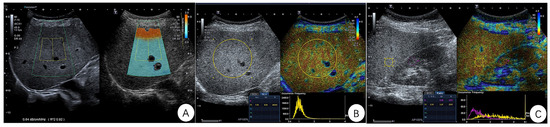

2.2. ATI, NLV and Ratio Examination